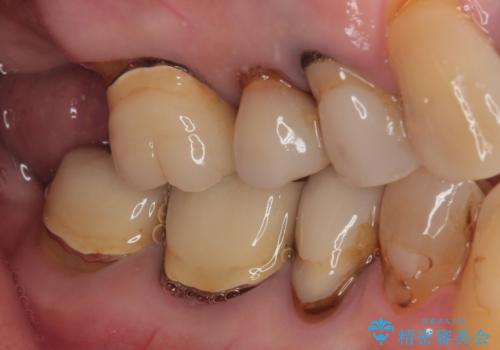

- 食事が取れないほどの激痛で、インプラント治療を希望して来院された患者様です。

近医にてクラウンを除去してもらった状態での来院でした。

遠心が歯根破折しており、歯槽骨が著しく吸収している状態であったため、抜歯即時でのインプラント埋入は断念し、2ヶ月ほど待機してから埋入することとしました。